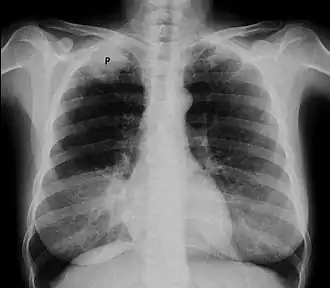

![]() Рентгенограмма органов грудной клетки, опухоль Панкоста (обозначена P, немелкоклеточная карцинома правого лёгкого) у курящей женщины 47 лет. | |

Опухоль Панкоста или опухоль верхней борозды лёгкого (это название чаще употребляется в англоязычной литературе) — рак первого (верхушечного) сегмента лёгкого с синдромом Панкоста.